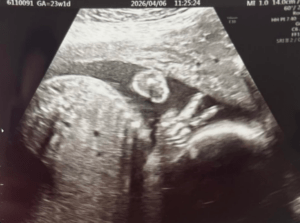

妊娠23週目の健診でのエコー写真を投稿したパパさん。お腹の赤ちゃんの成長は順調で、エコーで「性別も分かればいいな」と期待していたそう。

しかし、探っても探っても体勢の関係で性別はわかりませんでした。その際に映ったのが、ピースサイン。なんと、手が見事にピースの形になっていたのです。

エコーの写真(@hair_story.jpさんより提供)

ママさんも担当の先生も、画像を見た第一声は「可愛い!」でした。健診後にママさんは「今回は性別判明はしなかったけど、ピースで陽キャって判明してよかった〜!」と冗談半分に言っていたのだとか。